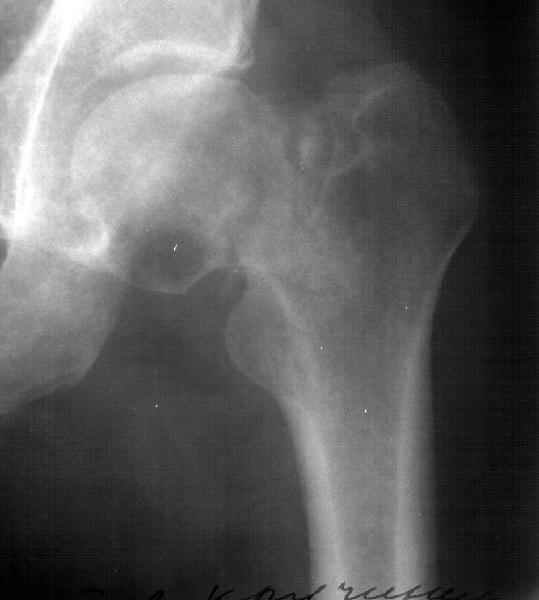

Глубокоуважаемые коллеги,

Вчера сделали остеотомию, делали близко к тому, как на той картинке.

Картинка тут.

То, что получилось, в приложении (без такой красивой анимации, к сожалению

;-)

result.jpg

34KB (35528 bytes)